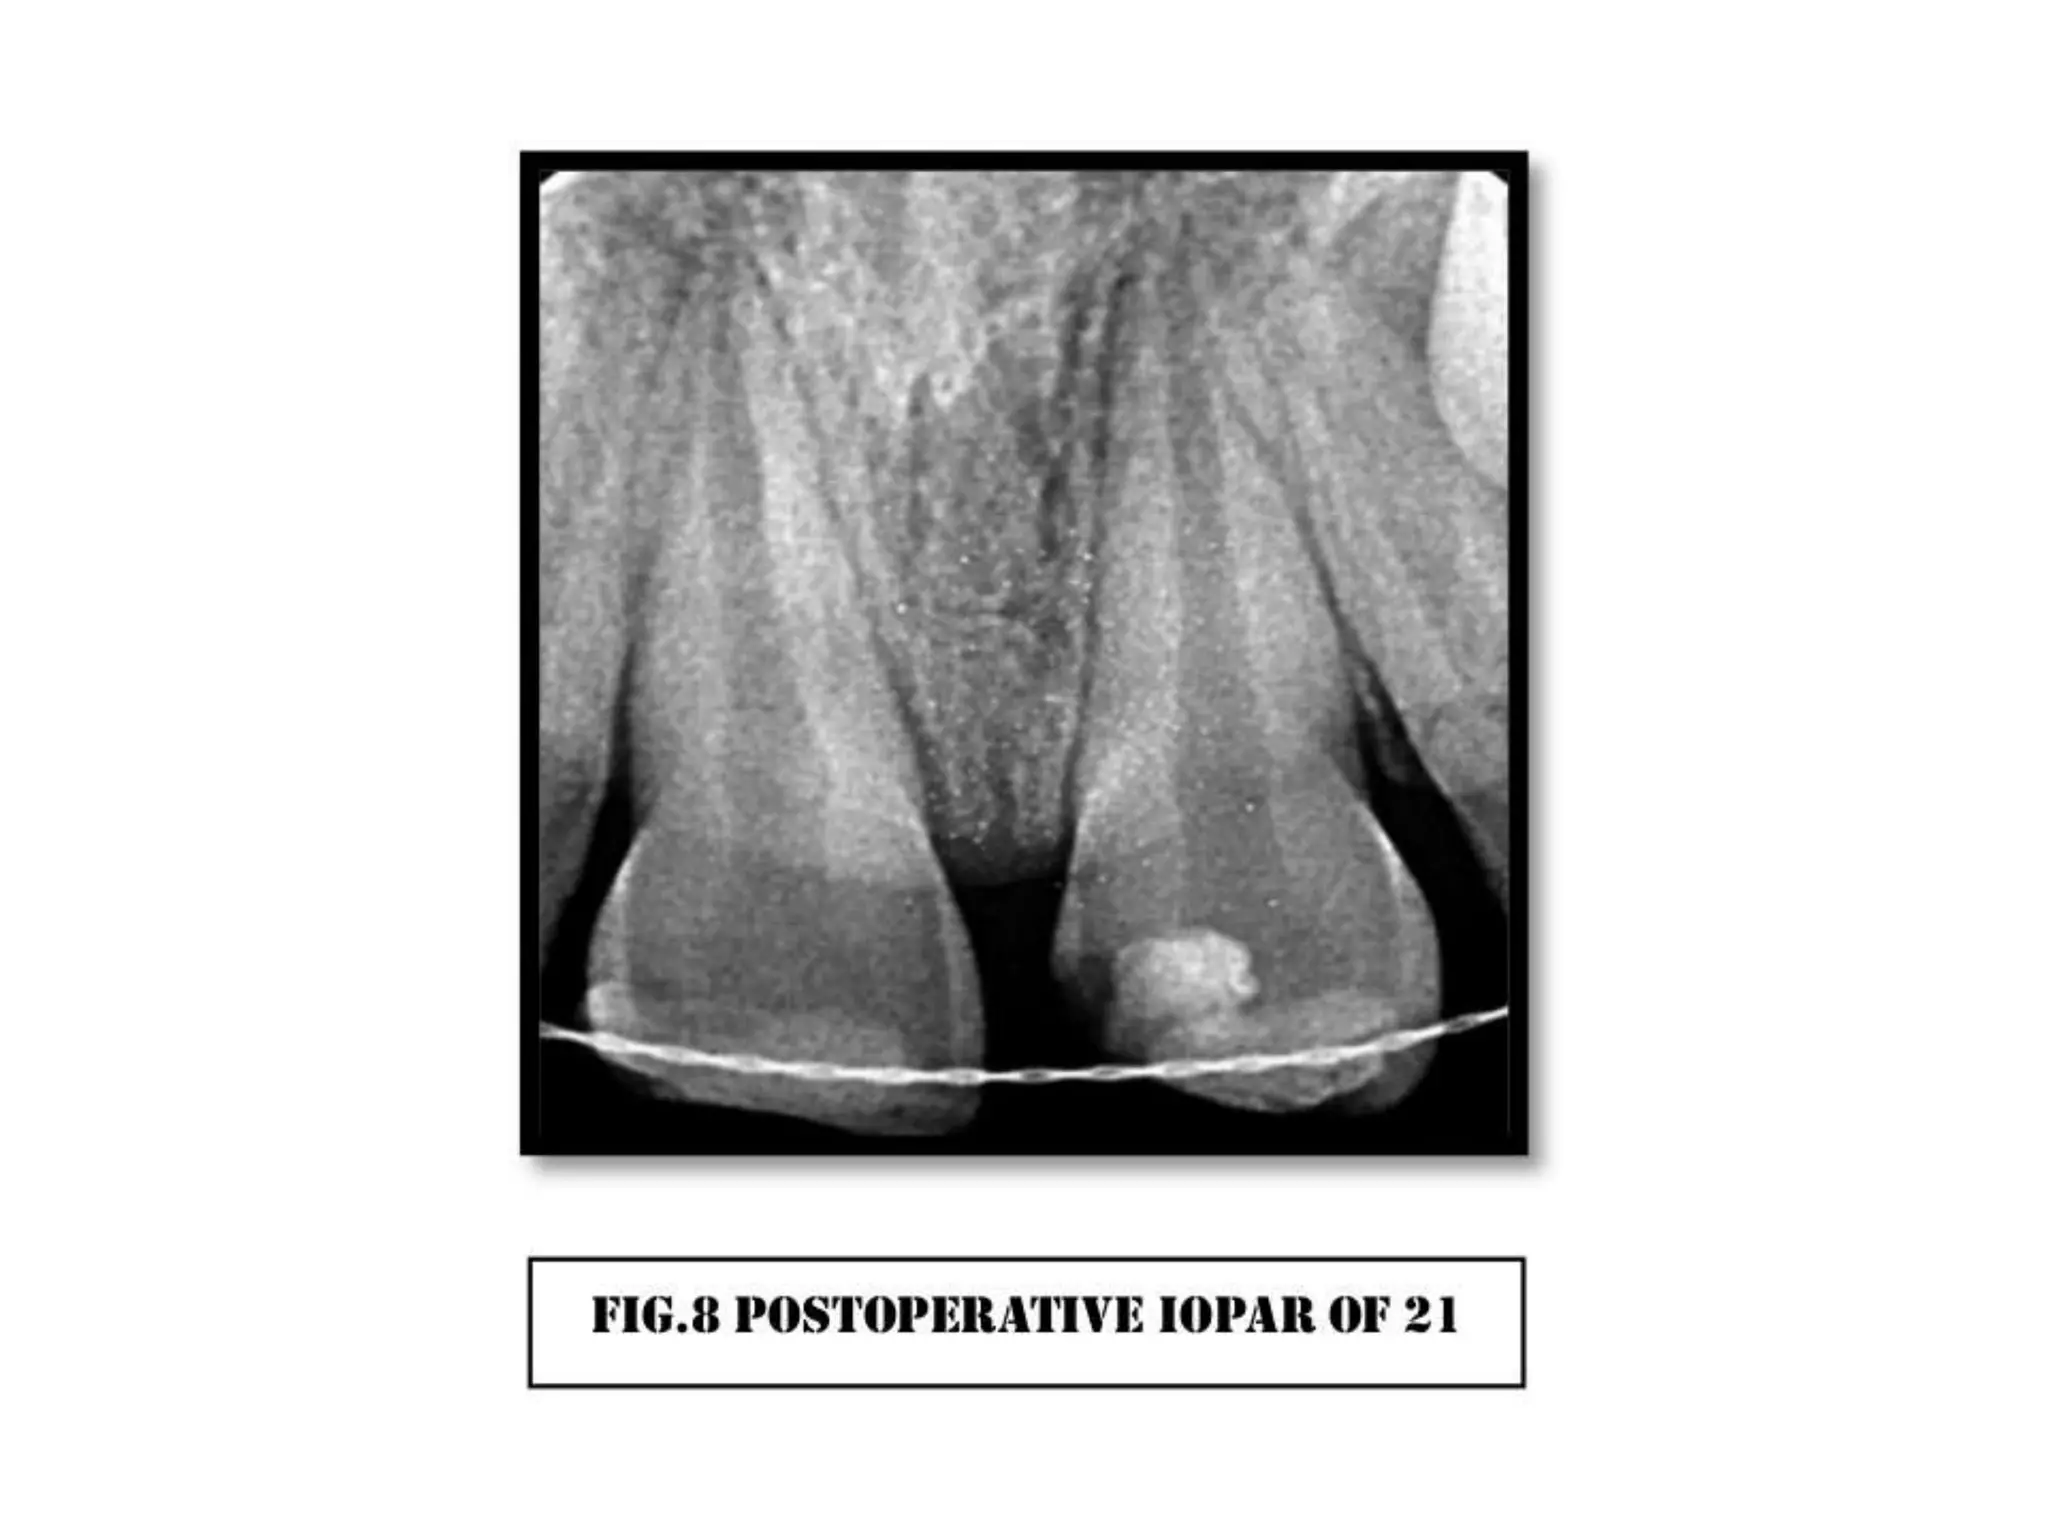

A case of cvek pulpotomy with mta

Case 1 CVEK PULPOTOMY

WITH MTA Dr. Roshni Maurya